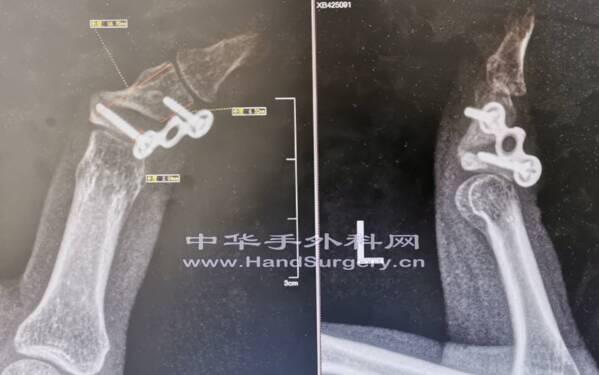

有何好办法治疗?内生软骨瘤刮除植骨(同种异体骨)钢板 固定术后

骨吸收,中节指骨畸形

今日手术基本按照设计方案进行的

只是中节指骨远端残留太少了,不能放置外架固定针

中节指骨基底骨片也非常薄了,仅残留基底关节面和软骨下骨

所有“门”型钉也少放了一枚

外固定架仅连接于近节指骨和远节指骨上,起到支撑作用